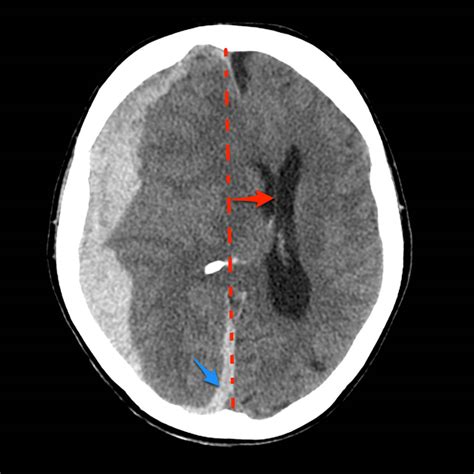

• Imaging Studies: Imaging techniques such as CT scans and MRI are crucial for visualizing the brain and detecting any shifts or abnormalities. These tests can provide detailed images of the brain’s structure and help identify the cause of the midline shift.